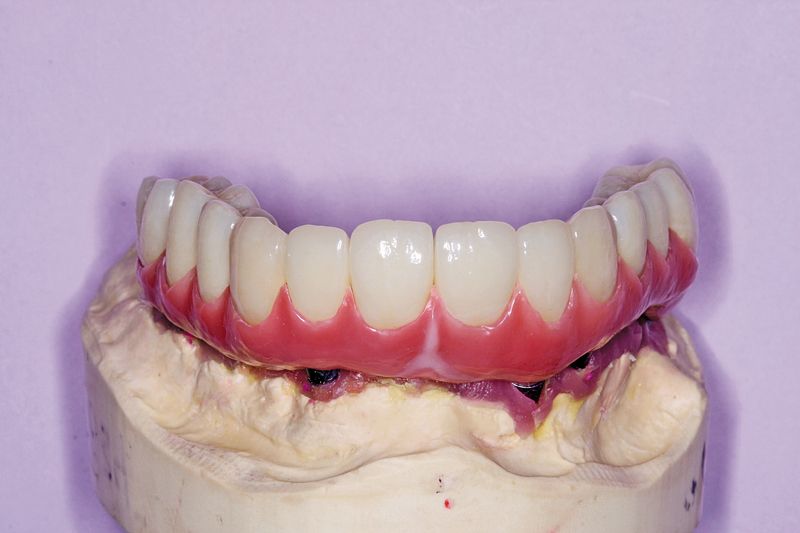

09 The patient had lost a significant amount of soft and hard tissue in the maxillary arch. To recreate the missing soft-tissue volume, the BellaTek Copy-Mill Framework was masked with an opaque, and zirconium silicate microceramic material (Ceramage, Shofu) was applied (Figs. 9 and 10). This material is available in an assortment of gingival colors that correspond to color variations in the natural dentition. The gingival mask was finished with standard abrasives such as stones and rubber wheels and polished.

Fig. 9?Facial view of the gingival microceramic material on the framework.

Fig. 10?Lateral view of the gingival microceramic material on the framework.

Fig. 13?The crown restorations in place on the BellaTek® Copy-Milled Framework.

11 The restoration and remaining crowns were returned to the dentist (Fig. 13). The BellaTek Framework was seated intraorally and secured with manufacturer-specific abutment screws. These were tightened to the appropriate torque per each manufacturer’s instructions. The implant-supported crowns corresponding to tooth Nos. 5, 8, and 12 were cemented with NX3 Cement (Kerr) while tooth Nos. 3, 4, 6, 7, 9, 10, 11, 13 and 14 were cemented with temporary cement so the screws could be accessed for removal, if necessary (Fig. 14). A panoramic radiograph was taken (Fig. 15).